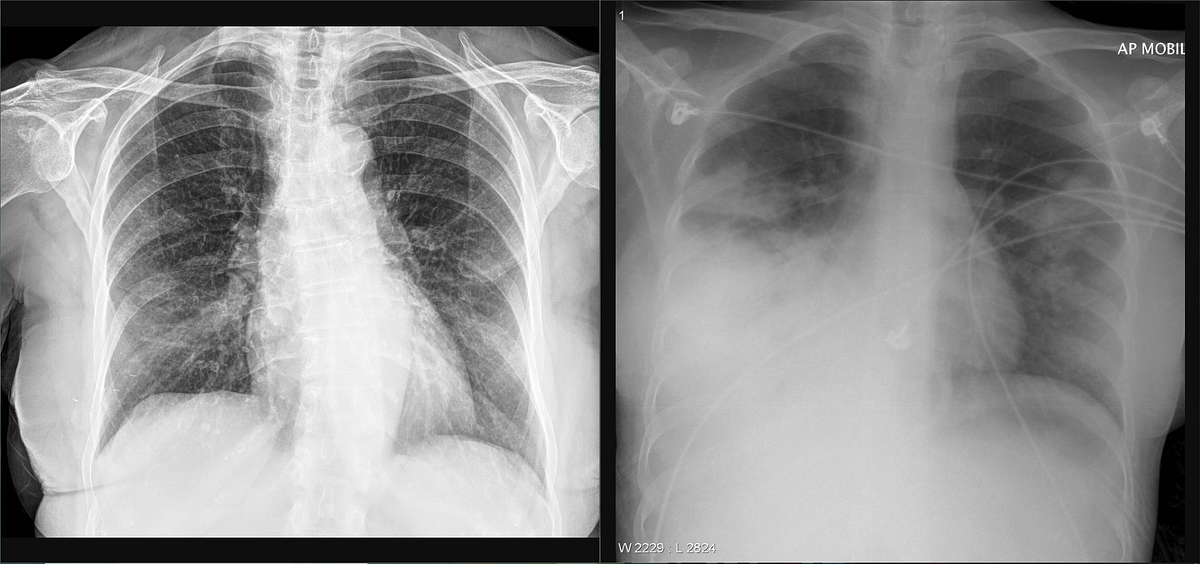

Radiographic and CT Features of Viral Pneumonia RadioGraphics